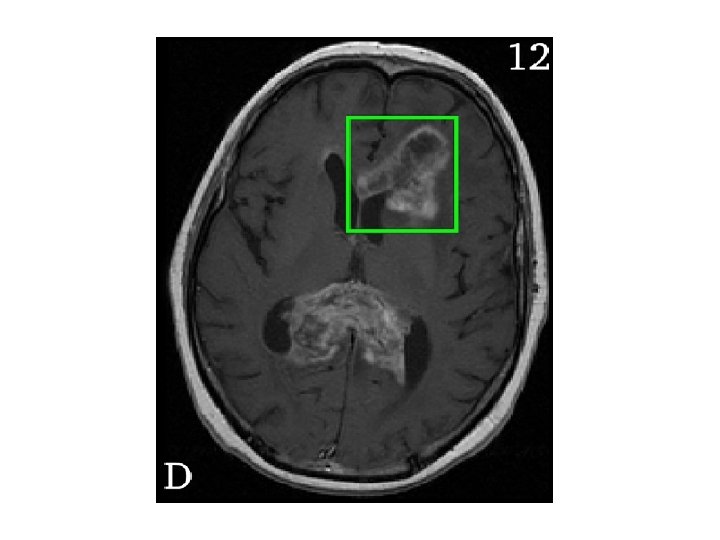

Anatomy and areas of contrast enhancement Edema

• Normal post-op changes – Enhancement – Gliosis – Oedema – Tumour bed enhancement due to high protein content – Pseudoprogression • Oedema / Infiltration - difficult to interpret the response to therapy specially after steroids.